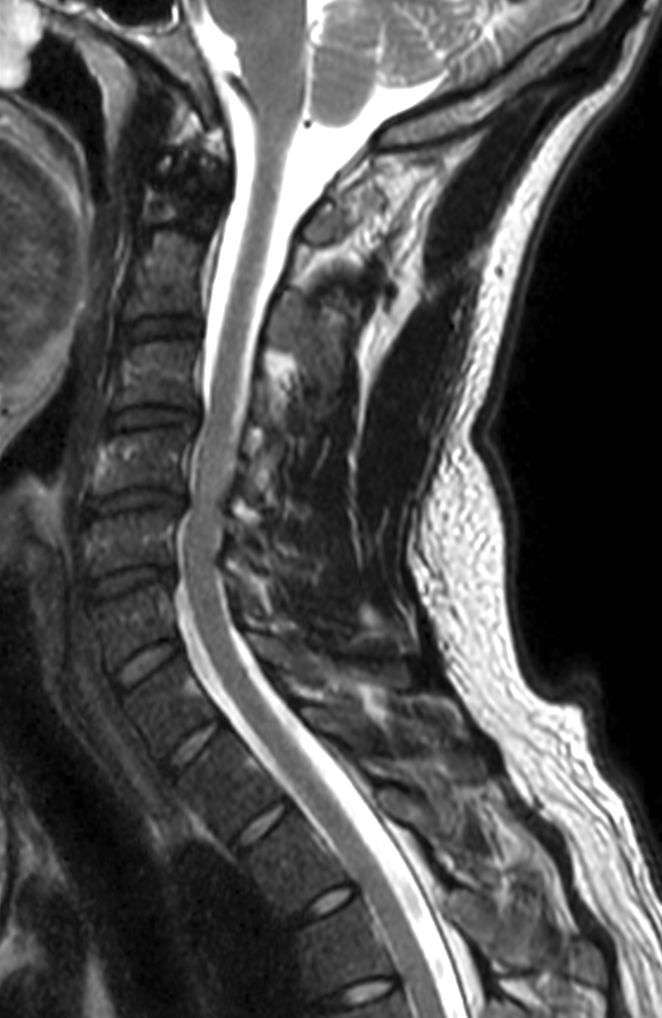

Cervical Spine with mDIXON XD

T2w TSE mDIXON XD (In Phase)